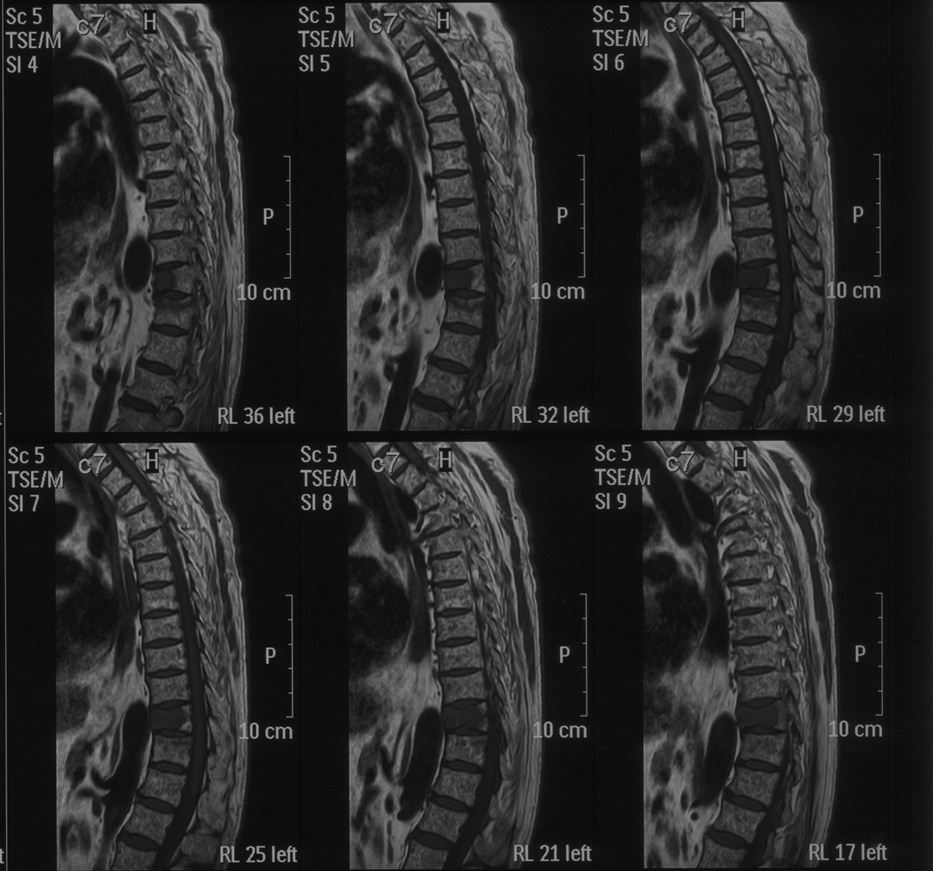

脊柱肿瘤图片

脊柱肿瘤图片,腰部肿瘤图片

脊柱肿瘤的影像学诊断

脊柱肿瘤的症状图片

脊柱转移瘤

脊柱肿瘤

脊椎里长瘤的症状图片